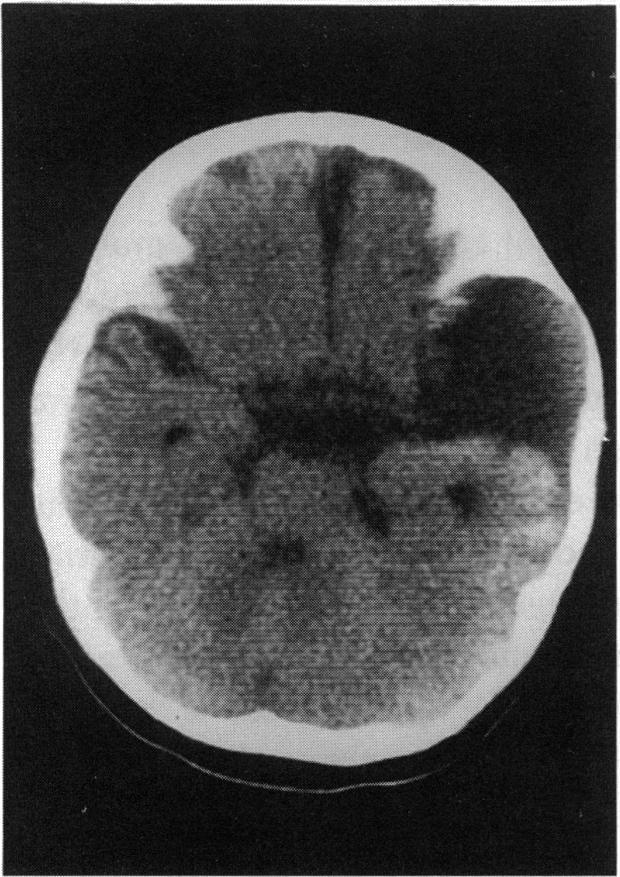

We identified five patients with the organoid nevus syndrome. Four had a classic sebaceous nevus in the facial and scalp area, and 2 had seizures and arachnoid cysts. All 5 patients had an epibulbar tumor, which proved to be a complex choristoma in one case that was studied histopathologically. A characteristic ophthalmoscopic feature, observed in the 4 patients with clear ocular media, was a flat yellow discoloration of the posterior fundus, of variable size and shape, which appeared to correlate with a dense plaque noted on ultrasonography and computed tomography. In 1 case, histopathologic examination showed that this posterior lesion contained intrascleral cartilage.

我们确定了5例器官样痣综合征患者。4例在面部和头皮区域有典型的皮脂腺痣,2例有癫痫发作和蛛网膜囊肿。所有5例患者均有眼球表面肿瘤,其中1例经组织病理学研究证实为复合性脉络膜瘤。在4例眼介质清晰的患者中观察到一个特征性的眼底镜特征,即眼底后部有扁平的黄色变色,大小和形状各异,这似乎与超声检查和计算机断层扫描中发现的致密斑块相关。在1例中,组织病理学检查显示该后部病变含有巩膜内软骨。